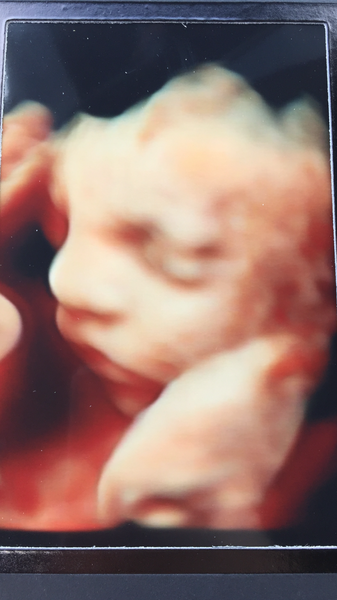

Well Girls. Meet my gorgeous little Boy!!!!

I’m so in love 😍

He has the most handsome little face I have ever seen! 💙💙

MagicalCreatures those are the best scan pics I've seen! Squish just shows us his feet or the back of his head!

@peachesarenom Thankyou. We were very lucky. At first he had all his limbs covering his face but the ladies were so fab and patient. And with a little help from a cold carton or orange juice (not Caprisun but good enough 😂) he woke up a little.